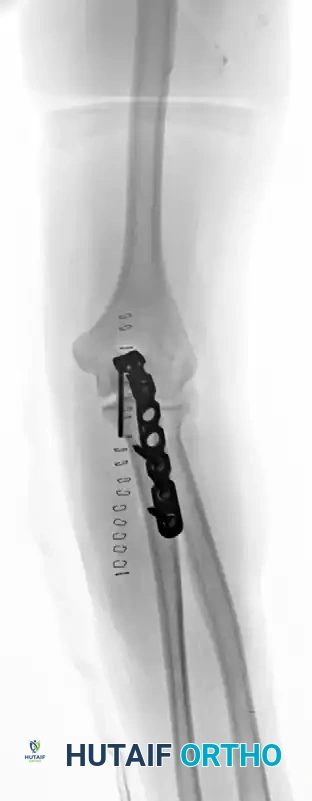

Complex Fracture-Dislocation of the Elbow (Pre-op AP):

Complex Fracture-Dislocation of the Elbow (Pre-op Lateral):

Fixation with Multiplanar Locking Intramedullary Nail (Post-op AP):

Fixation with Multiplanar Locking Intramedullary Nail (Post-op Lateral):